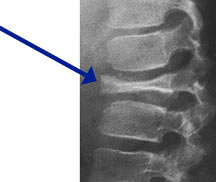

Hand-Schuller-Christian Disease

Triad:

- Destructive skeletal lesions

- Exophthalmos

- Diabetes Insipidus

- 10% of patients with unifocal EG develop multifocal and extraskeletal disease

- Usually <5 years old

- Hepatosplenomegaly, adenopathy, anemia, fever, neurological complaints

- Fatal in 15%

- Any bone but 90% have skull involvement